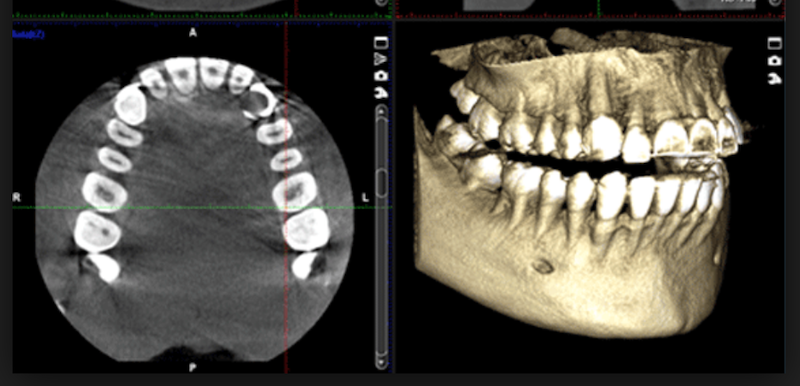

TAC Digital 3D

En Raga Valencia, los pacientes pueden realizar todas las pruebas radiológicas sin necesidad de desplazarse a otro centro. Nuestras instalaciones disponen de tecnología avanzada para la realización de TAC dental 3D digital.

El TAC dental 3D es una técnica diagnóstica que proporciona imágenes tridimensionales de alta precisión. Gracias a esta prueba, es posible visualizar con detalle huesos, dientes, nervios y tejidos blandos en una única captura, en menos de cinco minutos y con la comodidad de no tener que solicitar cita en una clínica externa.

Se trata de una prueba radiológica que genera imágenes tridimensionales de alta resolución mediante rayos X. La información obtenida se procesa digitalmente en un ordenador, lo que permite una visualización muy detallada. Gracias al TAC es posible analizar con precisión la ubicación de los dientes, el estado de los nervios, los tejidos blandos y los maxilares.

En Raga utilizamos un sistema de TAC de última generación basado en la tecnología C.B.C.T. (Tomografía Computerizada de Haz Cónico).

A diferencia del TAC convencional, que necesita realizar varias rotaciones alrededor de la cabeza y emite los rayos X en forma de abanico, el TAC C.B.C.T. emplea un haz de rayos X con forma cónica. Gracias a esta tecnología dental, una sola rotación completa de 360 grados es suficiente para recopilar toda la información necesaria y generar una imagen tridimensional precisa.